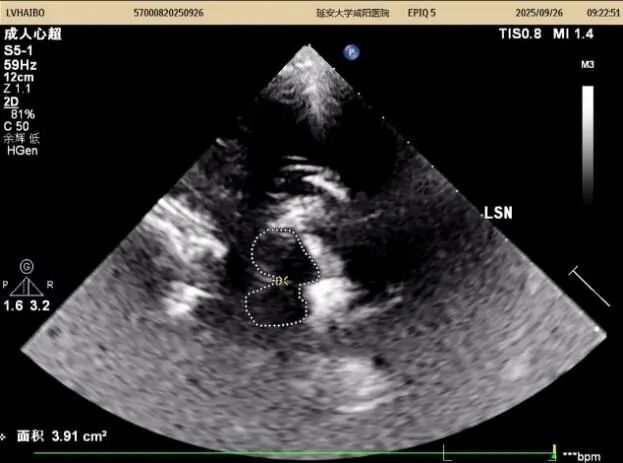

26日上午及下午14:00至15:50,以實際病例為媒介全流程質控,從設備調試、探頭的選擇與放置、中腦(黑質、紅核、導水管)、丘腦、第三腦室、豆狀核區域等的識別,到圖像優化與測量規范,逐步演示標準操作流程,重點解析黑質高回聲的識別與鑒別診斷。期間,結合患者病史,耐心答疑、細致指導,引導醫師多維度理解技術要點,提升實戰能力。同時對我科前期工作給予高度評價。

在專題授課環節,張教授以《帕金森病的TCS與神經調控專家共識-解讀與臨床應用》為題,從帕金森病的發病率及早期診斷難點切入,以問題為導向,結合國內外研究,系統講解了中腦黑質超聲的設備要求、檢查體位、標準切面及關鍵核團評估要點,并通過典型圖像與病例,深入闡釋影像特征與臨床表現的關聯。針對實際工作中常見問題進行了重點強調,現場學術氣氛濃厚。王英莉主任總結指出,開展TCS需做到“準、慢、細”—診斷精準、隨訪耐心、觀察細致,并強調各亞專業組應加強與臨床科室的縱深交流,融入科研思維。